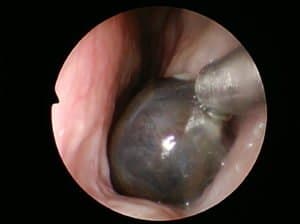

- Inferior turbinate hypertrophy: This is a normal structure present in the nose that is enlarged. You can occasionally see a lump present when you shine a light into the nose.